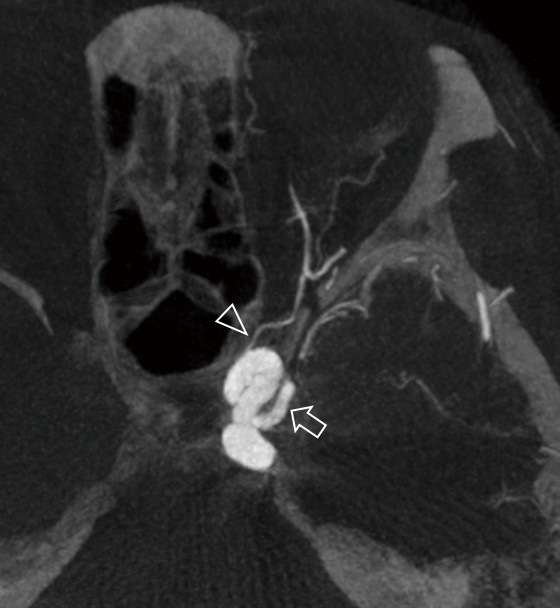

The accessory meningeal artery (AMA) demonstrates various potential anastomoses with the external (ECA) and internal (ICA) carotid arteries. However, rarely does the AMA markedly dilate and compensate for ICA blood flow. A 52-year-old woman with nonspecific symptoms was diagnosed with multiple cerebral aneurysms and abnormal blood vessels observed on magnetic resonance angiography. Digital subtraction angiography revealed four aneurysms and anastomoses between the left AMA and inferolateral trunk (ILT). In addition, two sequential severe flexions were observed in the cervical portion of the left ICA. No ischemic lesions were detected on magnetic resonance imaging. In conclusion, we experienced a rare case in which the AMA-ILT anastomosis was highly developed. This case also presented with the unusual characteristics of an anomaly in the extracranial ICA and multiple aneurysms.